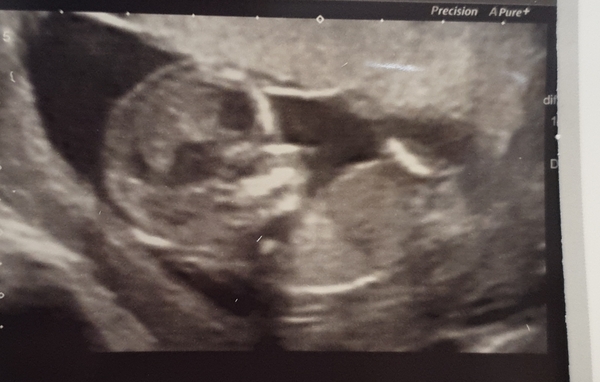

I had my final scan at the EPAU today at 10+5, measuring exactly to the day! I said to the sonographer are you 100% that everything at this point looks ok, and there is a heartbeat. She then showed me that “bean” was waving at me, and I burst into tears. The picture isn’t great, because it wouldn’t stay still, but you can see the arm up.

Wow @dressinggown87 that is such a clear pic, and so baby like for so early! Pleased you had such a positive experience 💞

@DressingGown87 thank you for sharing your gorgeous scan pic, it's so clear and it definitely looks like they're waving at you! I'm really glad you're feeling a bit more reassured and that you've been discharged from the EPU - it's an exciting / nervewracking feeling. Assume you don't need to wait long for your 12 week scan?